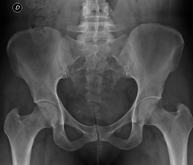

- Osteoarticular

Procedimiento que permite, mediante el uso de rayos X, y tras inyectar un contraste en el interior de la articulación, detectar lesiones de determinadas articulaciones (cartílago, hueso, tendones, etc.) según la distribución del contraste. - RX Pelvis

Procedimiento mediante el cual, utilizando rayos X, se obtienen imágenes de la pelvis para su estudio, especialmente de los huesos pélvicos. - RX Edad ósea

Estudio que, utilizando los rayos X, permite obtener una imagen de los huesos de la cadera y descartar luxaciones. - RX Seriada ósea